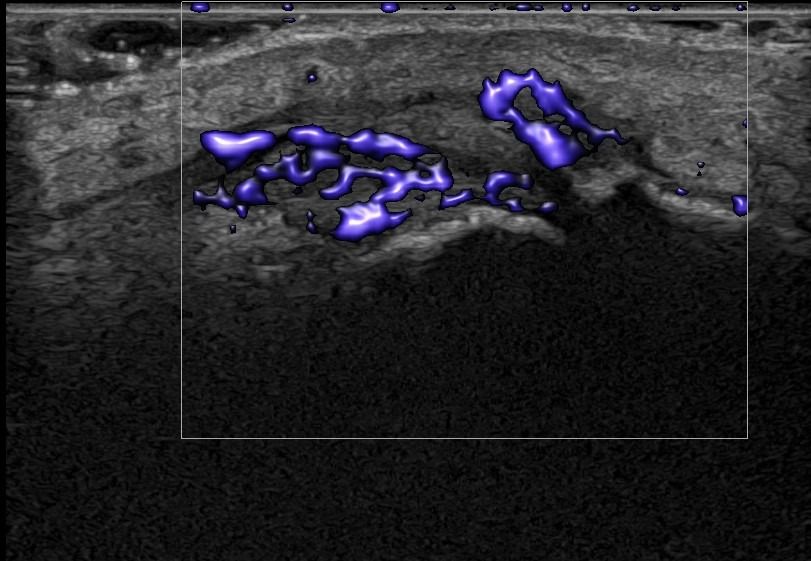

Rheumatic Diseases

- Rheumatoid Arthritis

- Psoriatic Arthritis

Dynamic Testing: Hand Ultrasound allows assessment of hand movement dynamically. This is particularly important for evaluating conditions affecting the range of movement, such as tendonitis and joint injuries.